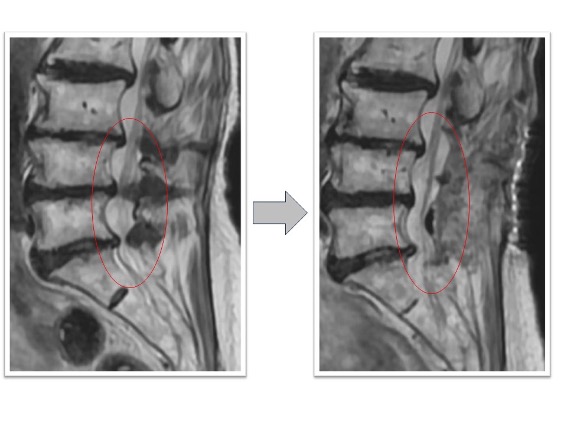

頚椎症性脊髄症

上肢の運動障害、歩行障害の患者様に対して頚椎椎弓形成術を実施。術後MRI画像で頚髄の圧迫が解除され頚髄前後にスペースが生まれています(図赤丸)。また、CT画像では術前後の比較で脊柱管の前後幅が約1.5倍以上に拡大していることが確認できます(図青矢印)。術後は歩行安定し、上肢運動も改善しています。